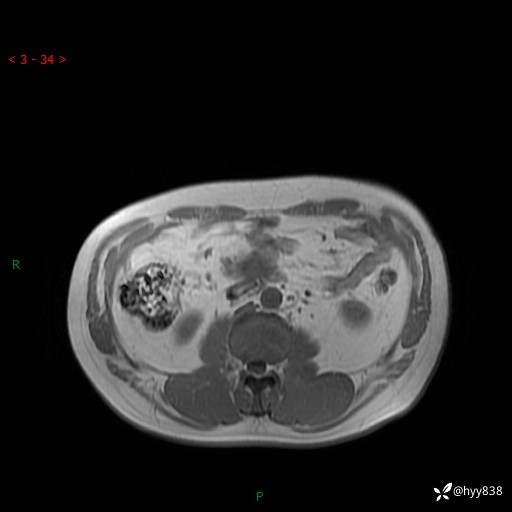

腹部CT平扫

MRI(T1WI+T2WIfs+DWI)